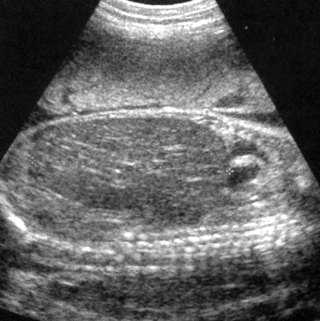

Υπερηχογραφικά, οι δύο νεφροί εμφανίζονται διογκωμένοι και υπερηχογενείς με

αναρίθμητες κύστεις στο φλοιό, διαμέτρου <2mm. Η έντονη υπερηχογένεια αποδίδεται

στην ενίσχυση των υπερήχων από τις μικροσκοπικές κύστεις (εικόνες 4, 5). Η νόσος

είναι αμφοτερόπλευρη και συμμετρική, αλλά υπερηχογραφική απεικόνιση της νόσου

μπορεί να μην είναι δυνατή πριν τις 24 εβδομάδες, γι' αυτό, συνεχόμενα υπερηχογραφήματα

απαιτούνται για να αποκλεισθεί η διάγνωση. Άλλα διαγνωστικά κριτήρια είναι η

απουσία της ουροδόχου κύστης και το ολιγοάμνιο.

| Εικόνα

4. Potter I, εγκάρσια διατομή. |

Εικόνα

5. Potter I, επιμήκης διατομή. |